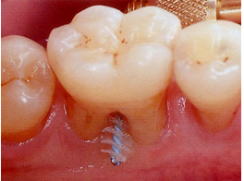

![]() |

麻酔下でのSRP後の歯肉からの出血は、臼歯部分岐部で多い |

根分岐部の歯石除去の困難性は、文献で証明されており、その結果、臼歯部分岐部は手術の可能性が高いことが示唆されます。